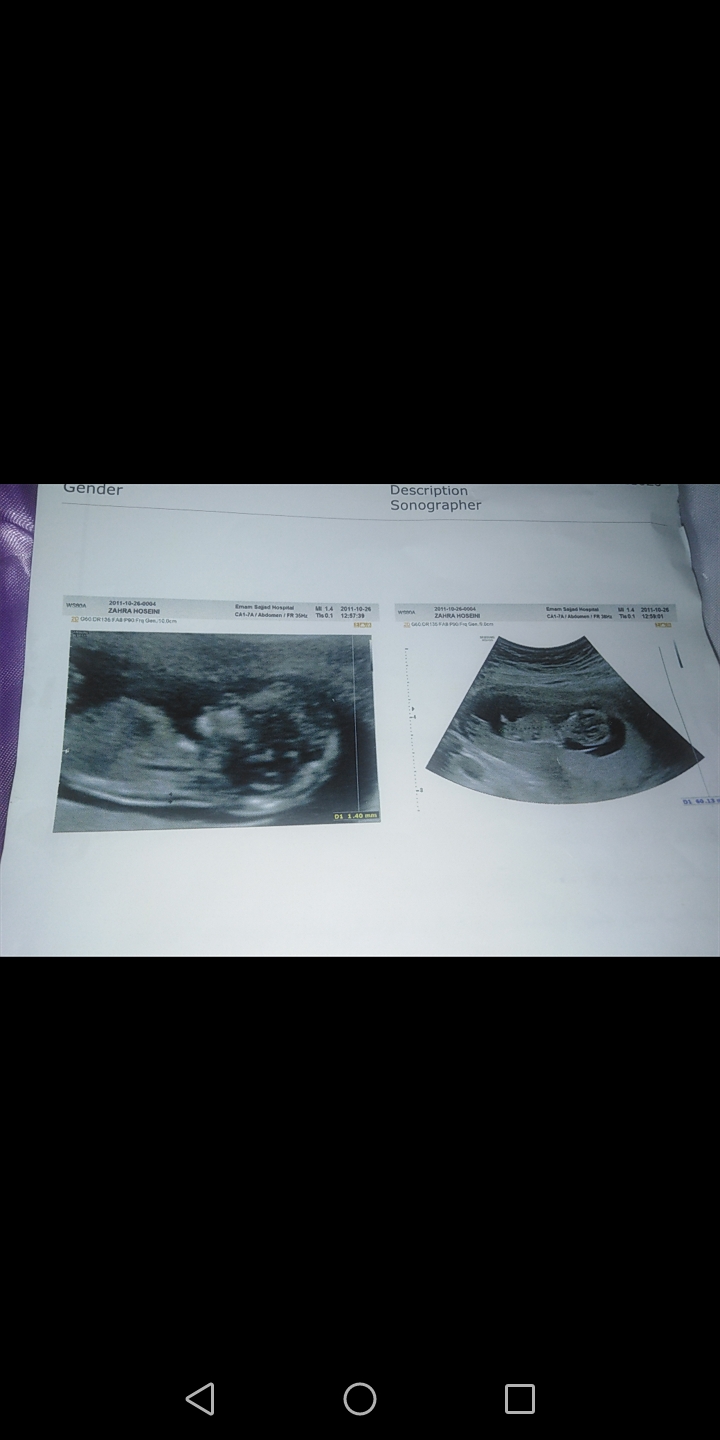

چرا دنبالش معلوم نیس  دکتر گف دختر یا پسر ؟ بنظر من جمجمش به دختر میخوره

نمیدونم سونوگرافی اینطوری عکس گرفته بیشتر تو بینیش وفضای پشت گردنش زوم کردن. همون ان تی و ان بی. نه هیچی نگفت منم نپرسیدم.